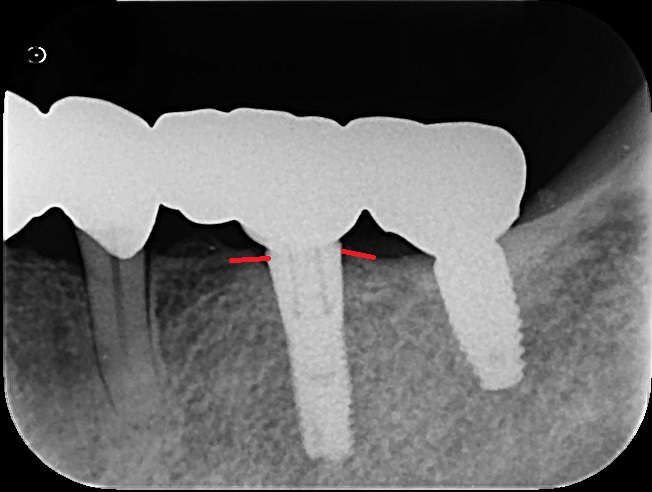

▼さらに詳しく見てみましょう インプラントを支える周りの骨(赤い線の部分)が、全く痩せていないのがお分かりいただけるでしょうか。これは、インプラント周囲炎などのトラブルがなく、骨が非常に健康な状態を保っている証拠です。

一般的に、10年以上良好な状態を保てれば「成功」と見なされる医療分野において、これは極めて良好な経過と言えます。